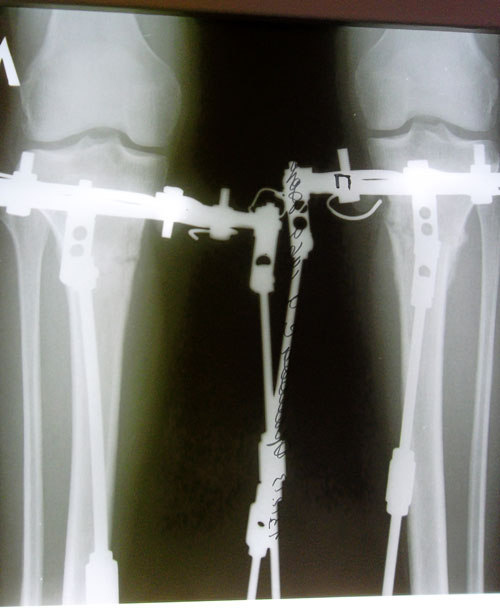

15- ый день после операции.

Вложения

SAM_6861.JPG